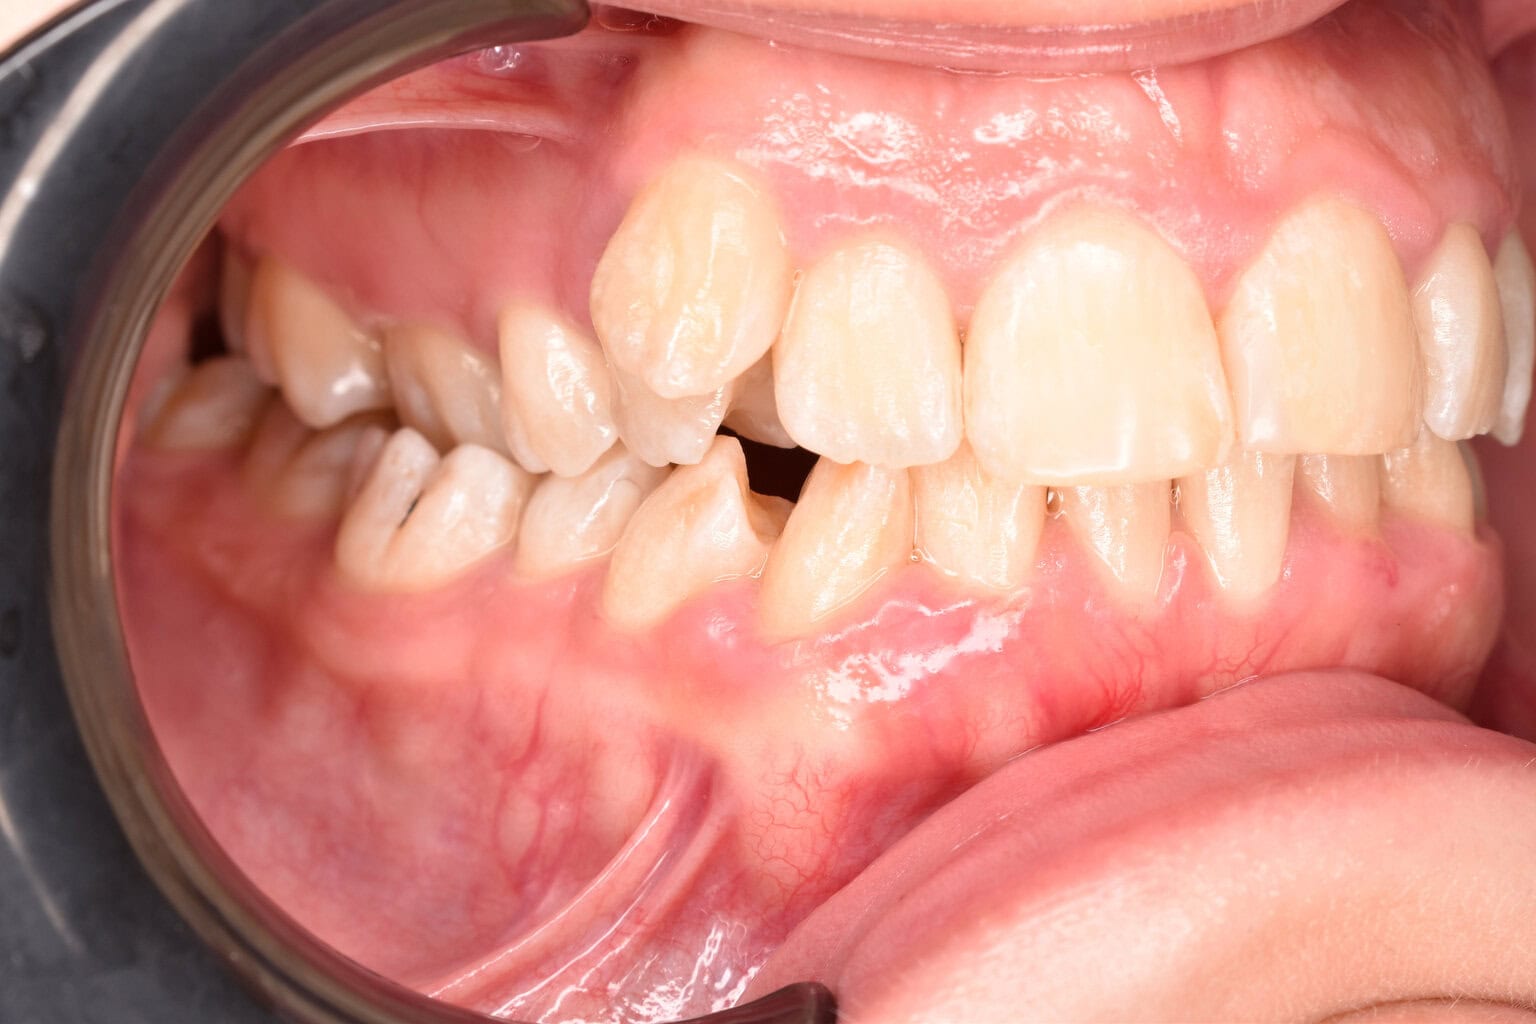

Vorher-Nachher-Ergebnisse

Echte Ergebnisse. Echte Menschen.

Jede Behandlung bei TIEFBLAU Kieferorthopädie ist so individuell wie der Mensch dahinter. In unserer Vorher-Nachher-Galerie zeigen wir Ihnen echte Behandlungsergebnisse aus unserer Praxis in der Kölner Südstadt: Schonend erzielt, präzise geplant und mit dem Anspruch, den wir seit über 40 Jahren an jede Behandlung stellen.

Die Bilder geben Ihnen einen Eindruck davon, was moderne Kieferorthopädie leisten kann, ob bei Kindern, Jugendlichen oder Erwachsenen.

Der sichtbare Unterschied

Dokumentiert. Überzeugend. Nachhaltig.